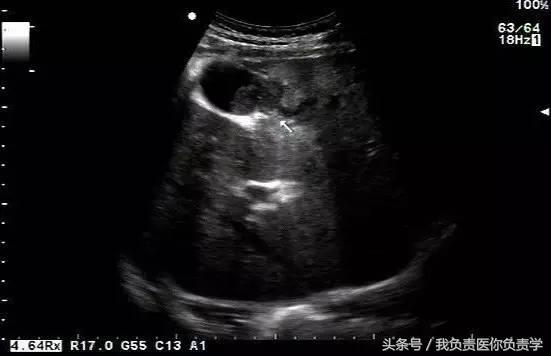

典型病例 1

患者男,64岁,因右上腹疼痛半月余就诊。查体发现右上腹部轻压痛,无发热。超声检查所见如下:

图1示胆囊增大,囊壁增厚,囊内透声差

图2示于胆囊外侧可见一局限性囊性无回声区

图3示胆囊与囊性回声区间隐约可见裂隙相通

图4和5为局部放大图像,可见胆囊与囊性回声区间可见直径约2mm的通道

超声检查考虑为胆囊炎合并胆囊穿孔,后经CT检查证实。